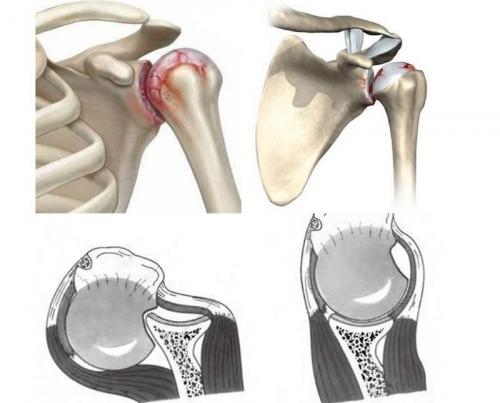

Повреждение либо субхондральный перелом Хилл-Сакса — дефект головки плечевой кости, являющийся последствием вывиха плеча .

Во время травмирования происходит ограниченный вдавленный (импрессионный) перелом головки кости плеча. Механизм повреждения заключается в следующем: из-за травматического воздействия головка кости перекатывается через острый край суставной впадины лопатки.

Если дефект обширный, то в дальнейшем он может способствовать рецидивирующей нестабильности плеча в положении отведения и вращения руки.

- При данном травмировании зачастую происходит импрессионный перелом головки кости.

- Длительное нахождение кости в неестественном положении способствует увеличению дефекта.

- При повторных вывихах наблюдается увеличение дефекта.

Импрессионный перелом Хилл-Сакса является самым частым дефектом при заднем вывихе. Согласно статистике он возникает в 86% случаев.

Дегенеративно – дистрофические патологии, выраженные в изменении головки мыщелка, вследствие различных повреждений – вывиха или импрессионного перелома классифицируются, как повреждение Hill-Sachs. Стабилизация плечевого сустава при повреждении Hill-Sachs требует серьезного подхода к лечению.

Особенности стабилизации плечевого сустава при повреждениях Hill-Sachs, во многом зависят от механизма проявления патологий. Это могут быть:

- продавливание вмятины в головке мыщелка розеткой лопатки (суставная впадина), в результате неудачного переката головки при вывихе;

- перелом плечевого сустава, в результате дефекта головки (данная патология проявляется, как осложнение вывиха);